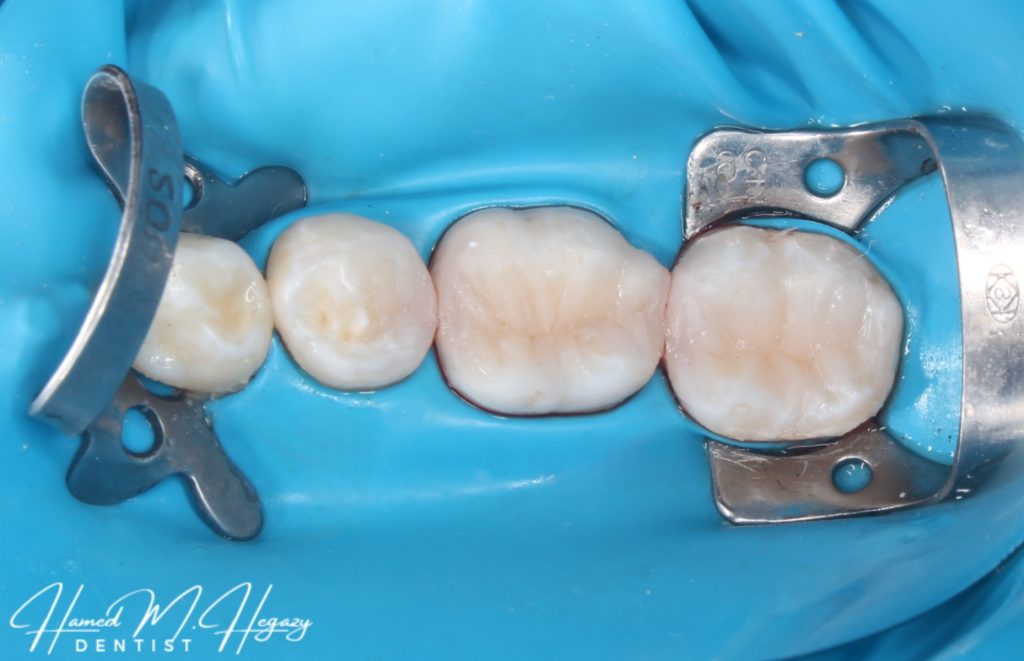

Obturation and cavity design

Composite restoration build up